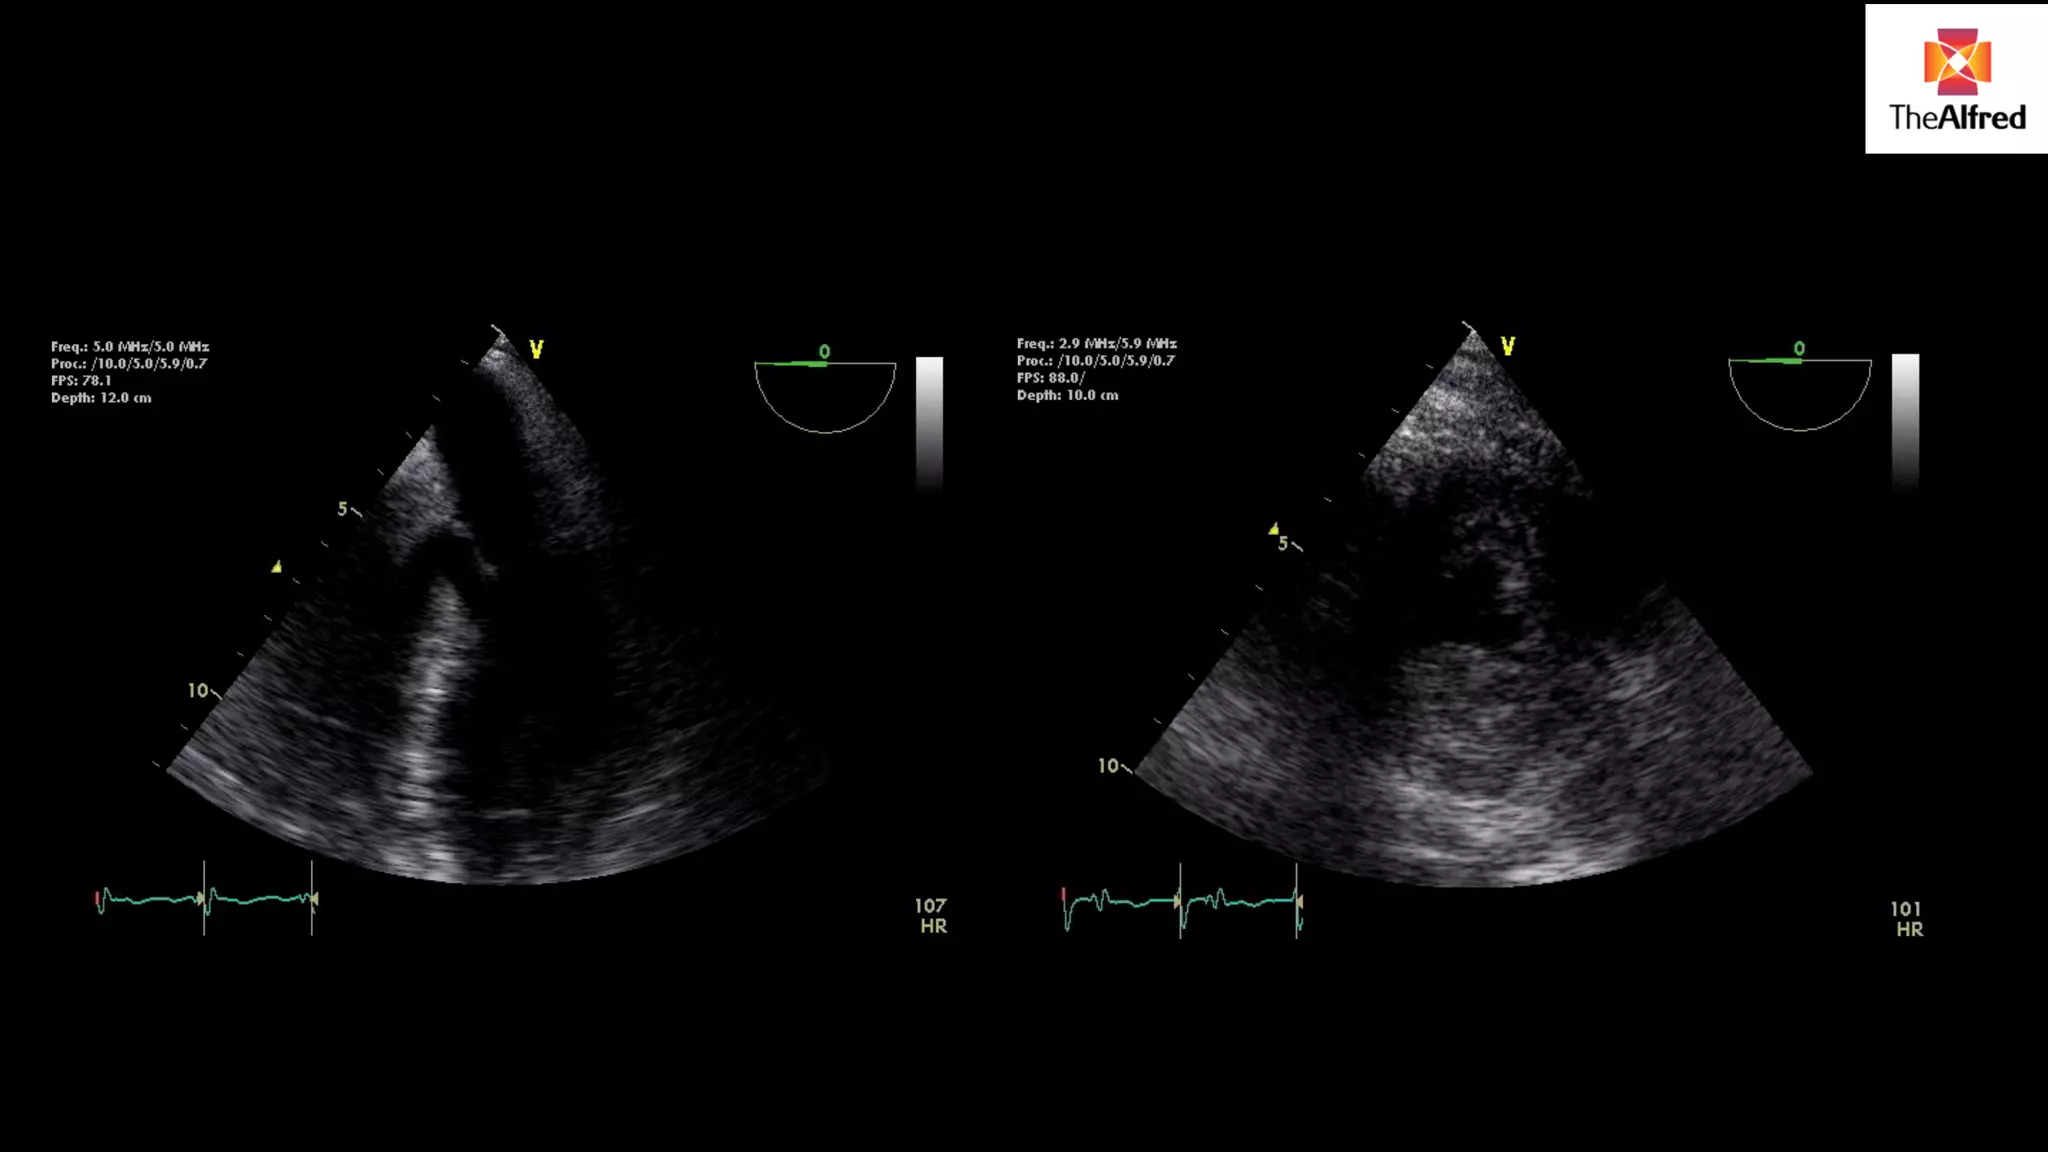

USE VIEW WITHTHE BEST DOPPLER LINE UP- DIFFERENT FOR DIFFERENT PATIENTS 5 chamber view 3 chamber view

5 chamber

view

3 chamber